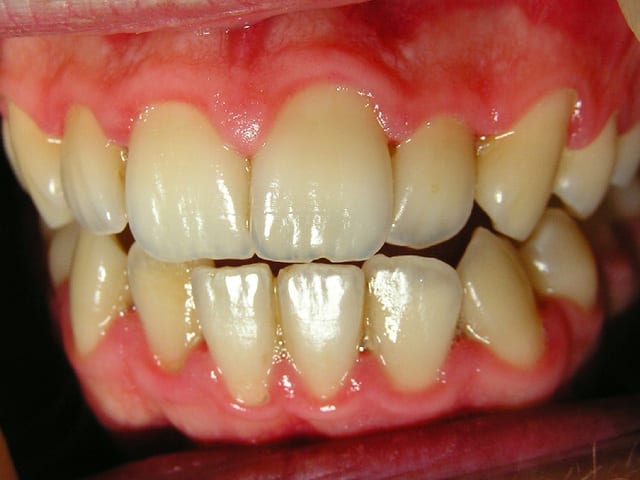

J'ai ressorti les photos prises initialement:

22/06/2005 à 02h01